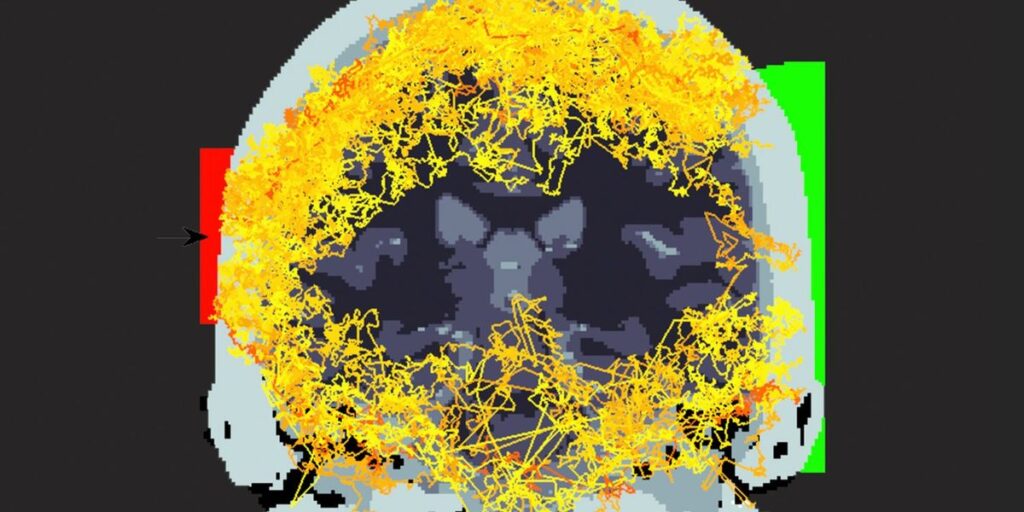

It took many iterations of experimental setups to definitively find the one in a billion billion photons that make it through the head.Extreme Light group/University of Glasgow